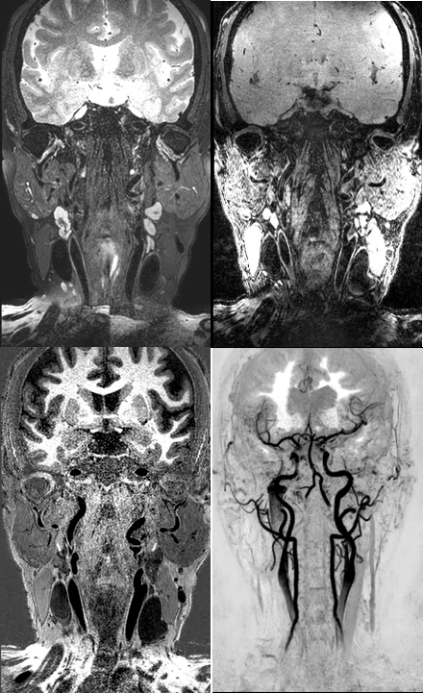

高分辨血管壁成像技术清晰显示椎动脉及基底动脉粥样硬化并斑块形成至管腔狭窄 磁共振高分辨血管壁成像技术显示左侧大脑中动脉 M1 段内血栓致左侧大脑梗塞

磁共振高分辨血管壁成像技术清晰显示左侧大脑中动脉 M1 段炎性增强及管腔狭窄 左侧颈内动脉路外段动脉夹层,可观察到真假腔、内膜片和周围炎性渗出 磁共振大范围高分辨血管壁多对比度成像技术